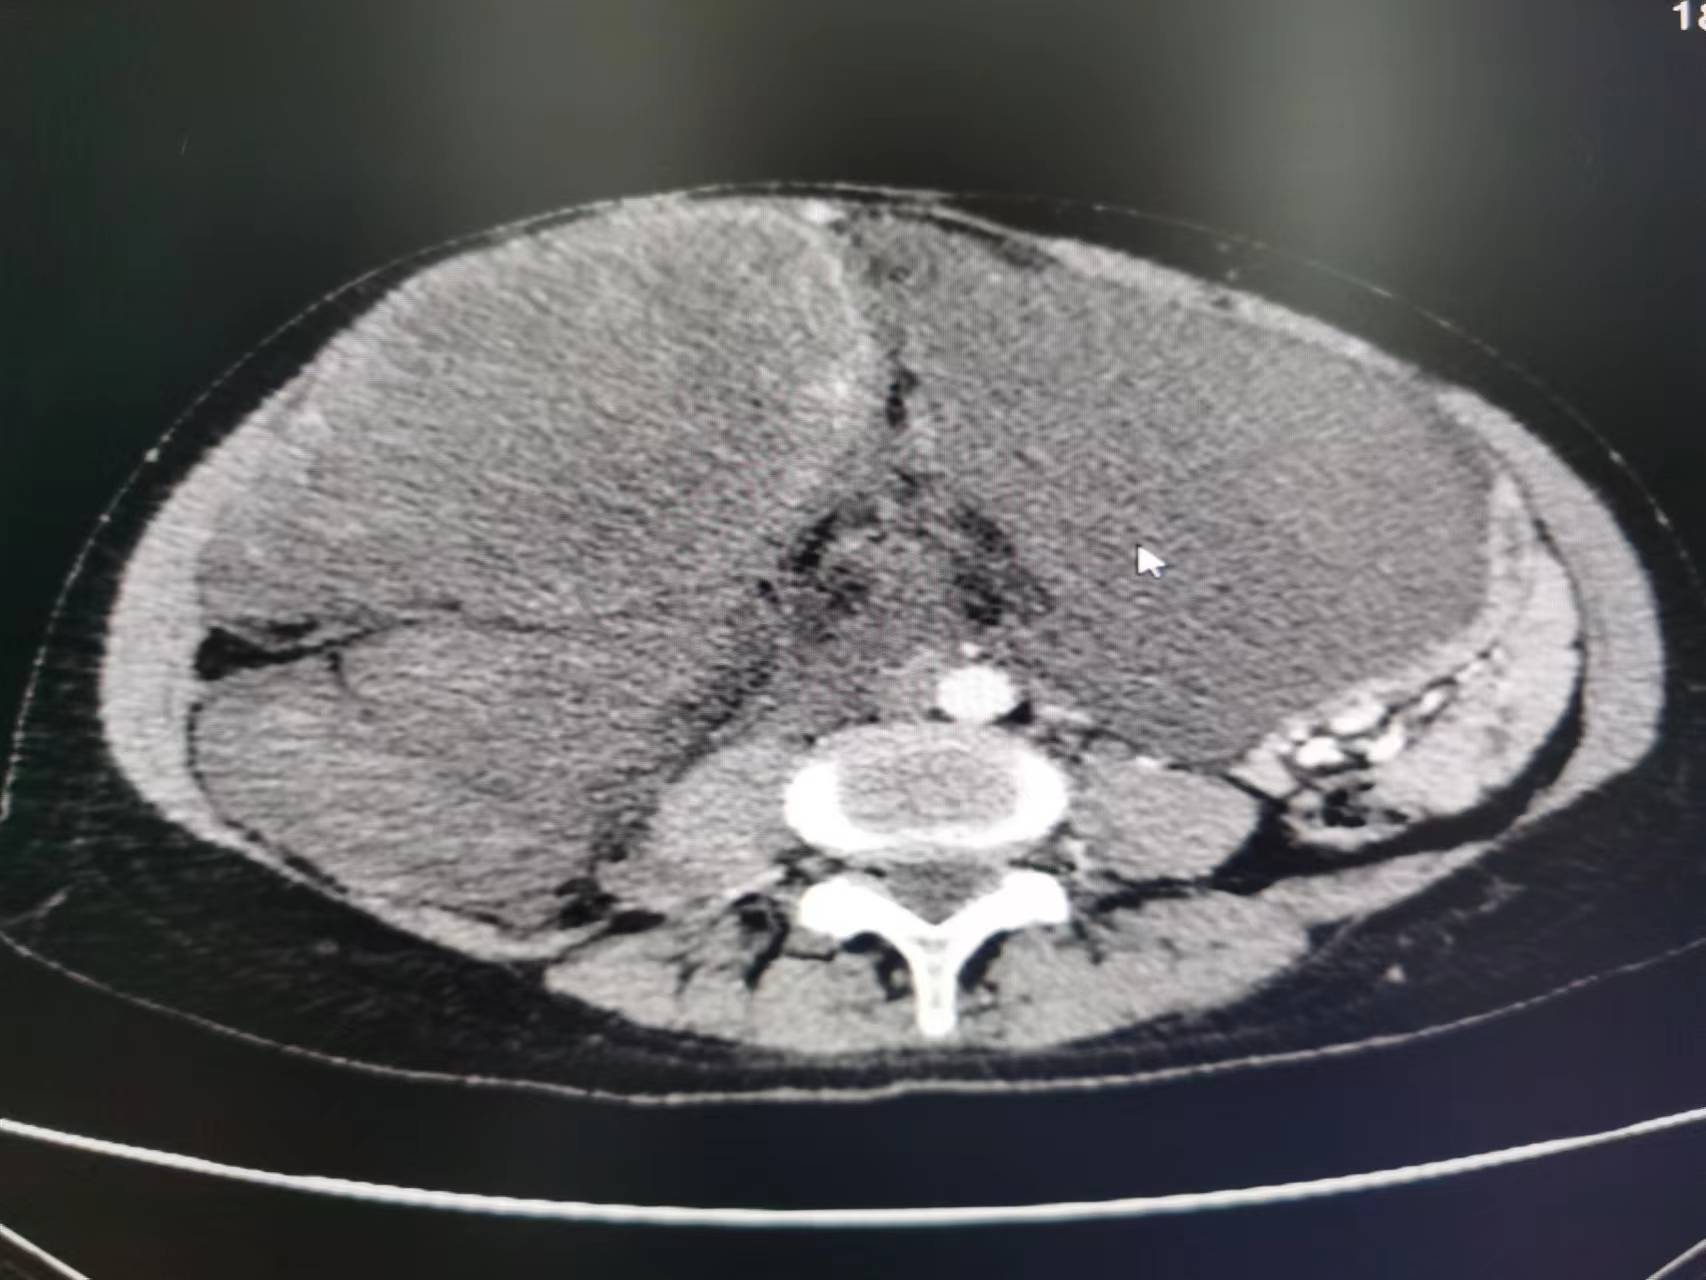

患者64歲,因腹脹就診。查體觸及一個大腫物,CT掃描提示巨大腫瘤,占據(jù)整個腹腔,導致臟器移位。腫瘤表現(xiàn)為后腹膜肉瘤,沒有進行活檢。完整切除了這個40cn90磅的腫物,同時進行了左側腎臟廣泛切除和左側結腸切除手術。手術病理符合R0切除的III級后腹膜脂肪肉瘤?;颊咝g后恢復順利,無并發(fā)癥出院。腹膜后肉瘤是少見腫瘤,年發(fā)病率為千萬分之三。手術完整切除腫瘤是治療的關鍵,5年生存率可以達到50-70%?;熀头暖煟瑢τ诓糠只颊哂行?,特別是交界性,或無法切除的腹膜后肉瘤。沒有證據(jù)證明大體腫瘤完整切除后,再進行術后放療有價值。

腹膜后脂肪肉瘤做了四次手術后又復發(fā),手術還能不能做?能不能完整切除腫瘤?

大家好,近日遇到了一位腹膜后脂肪肉瘤的患者,該患者做了四次手術,又面臨復發(fā)?有很多患者及家屬猶豫,患者還能不能手術?腫瘤還能不能完整切除?這不僅是廣大患者面臨的問題,也是醫(yī)生需要考慮的問題,今天就和大家溝通一下,為什么有的患者反復做手術,手術后沒有過多久,腫瘤又長了出來?這是一位做過四次手術的腹膜后脂肪肉瘤患者,很不幸,第四次手術后不到1年,就發(fā)現(xiàn)腫瘤又長了出來。大家知道,目前腹膜后脂肪肉瘤沒有很好的藥物來控制腫瘤的生長,所以患者來就診時腫瘤已經(jīng)長的很大了,占據(jù)了腹腔的一半以上,患者出現(xiàn)了腹脹,進食困難的情況。通過術前檢查我們分析患者需要手術,同時腫瘤有很大的概率能夠完整切除?;颊唠m然很不幸,但是探查發(fā)現(xiàn)腫瘤雖然很大,侵犯了結腸,同時侵犯了右側腎臟,有近30cm,但是能夠完整切除。經(jīng)過治療團隊的共同努力,患者的腫瘤被完整切除,家屬和我們都很高興,同時患者術后恢復的也很順利。下面就和大家普及一下腹膜后脂肪肉瘤的手術的一些問題。首先,腹膜后脂肪肉瘤的患者第一次手術非常關鍵,第一次手術切除的完整性和徹底性是患者不復發(fā)或者延緩復發(fā)的關鍵。第二:因為腹膜后腫瘤可能侵犯胃腸道,腎臟,輸尿管,膀胱甚至子宮,所以腹膜后腫瘤的手術涉及多個學科。不管就診到胃腸科、泌尿科還是婦科,都不可能單獨完成此類手術,有可能會存在姑息切除的可能性,這也是導致腹膜后腫瘤患者手術不徹底,近期復發(fā)的因素之一。目前很多醫(yī)院還沒有成立專門的腹膜后腫瘤科,所以腹膜后腫瘤的患者就診時就不知道該掛哪個科室?第三對于復發(fā)的腹膜后腫瘤患者,是不是發(fā)現(xiàn)復發(fā)就要做手術呢?從目前的研究看,對于復發(fā)的患者不是一發(fā)現(xiàn)復發(fā)就要做手術。如果復發(fā)的腫瘤長到很大了,影響患者生活了,或者腫瘤如果再生長,就要侵犯到某些導致手術風險增大很多倍的臟器了,這個時候還是要選擇盡早切除腫瘤。第四對于復發(fā)的腹膜后腫瘤,是不是就不能完整切除了,答案是不一定。通過術前的閱片,手術探查,有很多患者是可以完整切除腫瘤的。目前我們治療團隊隸屬河南省腫瘤醫(yī)院普外科,一直從事腹膜后腫瘤的治療,積累了大量的臨床經(jīng)驗,希望能解決此類患者的問題。有此類需求的患者可以通過好大夫平臺或門診前來咨詢就診。